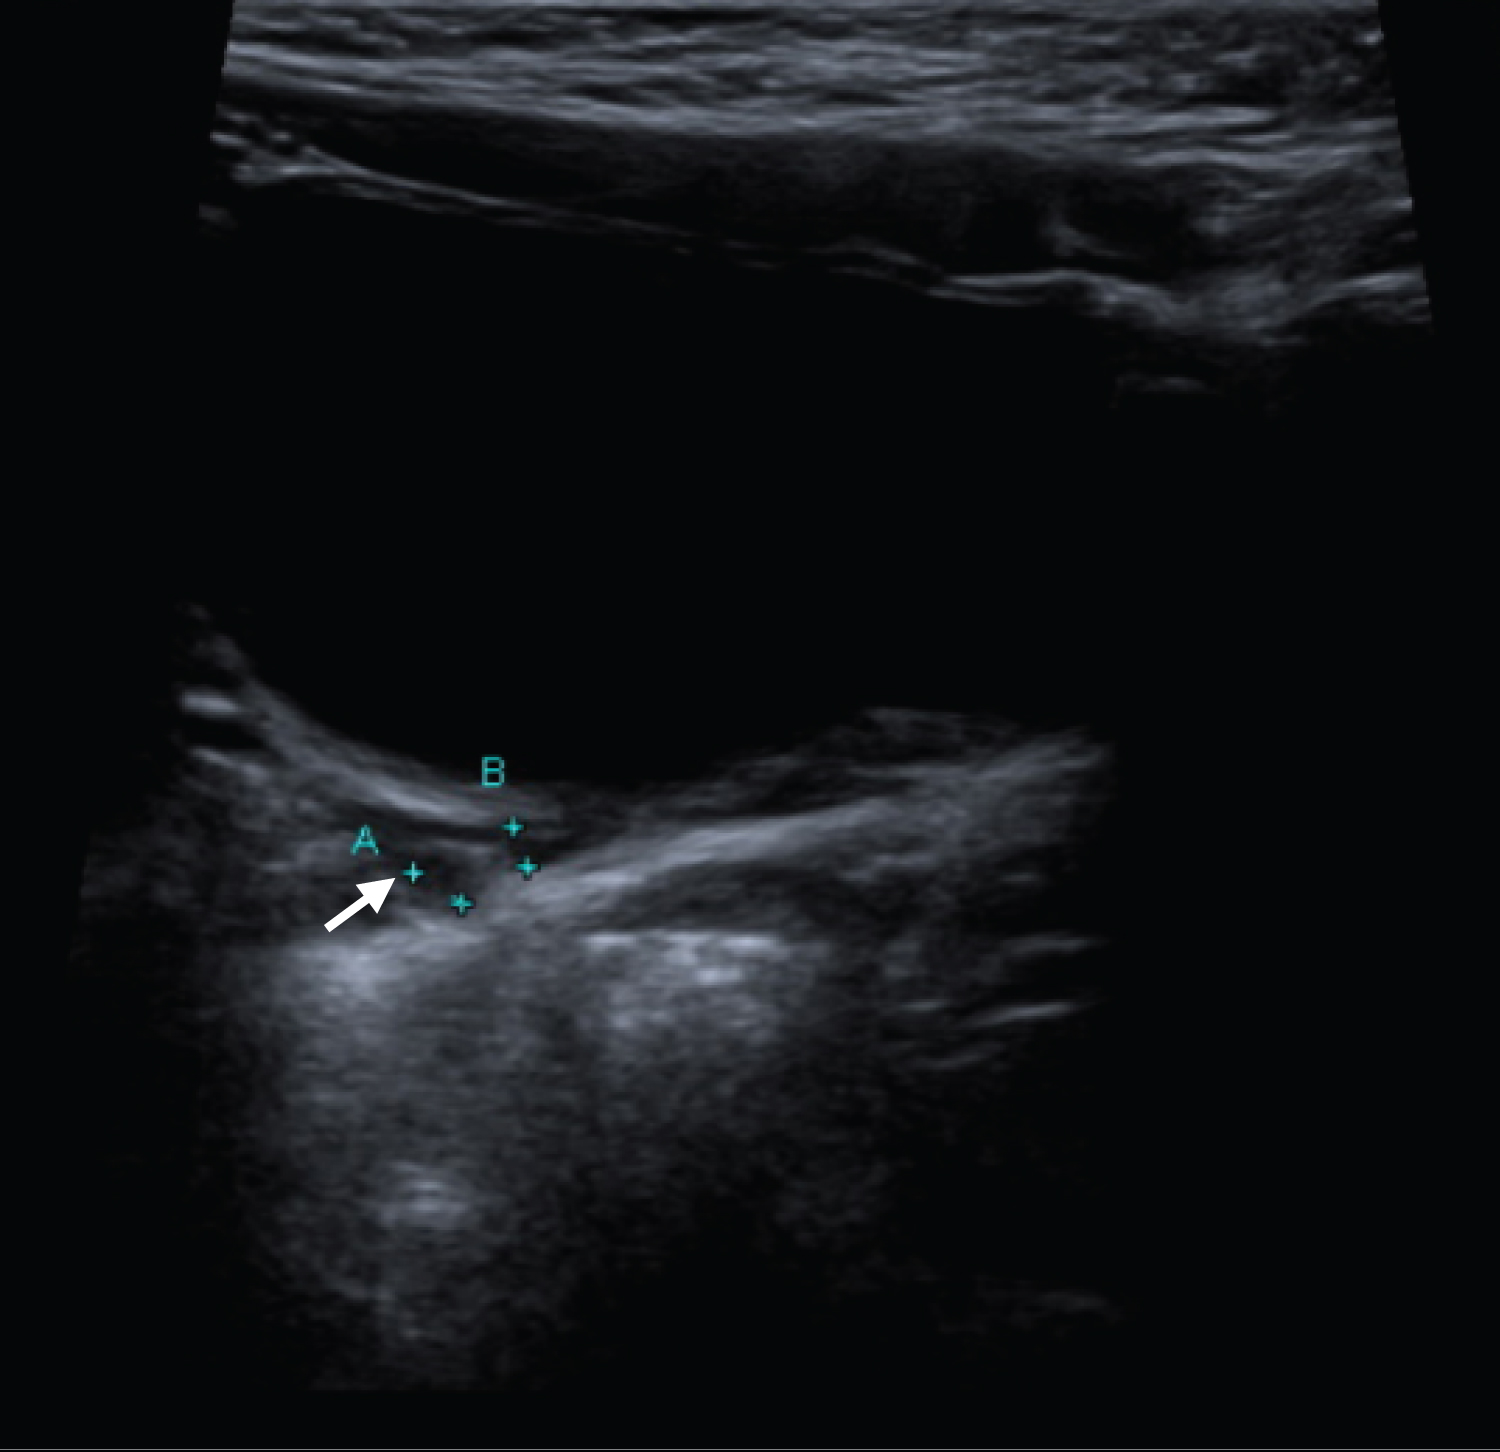

We present a case of an 8-year-old male child, with irrelevant family history, and a prenatal diagnosis of solitary kidney- right renal agenesis. He performed a renal and bladder ultrasound at 4 weeks of life, which confirmed the presence of right renal agenesis and left kidney with mild vicarious hypertrophy, without other alterations. He also performed DMSA renal scintigraphy, which confirmed right renal agenesis (Figure 1). He began follow-up in a pediatric nephrology consultation and at 10-month-old, a renal and bladder ultrasound identified a solitary kidney and a globose right seminal vesicle, with a cystic appearance (Figure 2), alterations compatible with Zinner syndrome. The patient remains asymptomatic and without alterations in the physical exam, performing ultrasound control every 6-12 months, presenting alterations compatible with Zinner syndrome.

Figure 2: Suprapubic bladder ultrasound, showing the right seminal vesicle with a cystic appearance (white arrow).